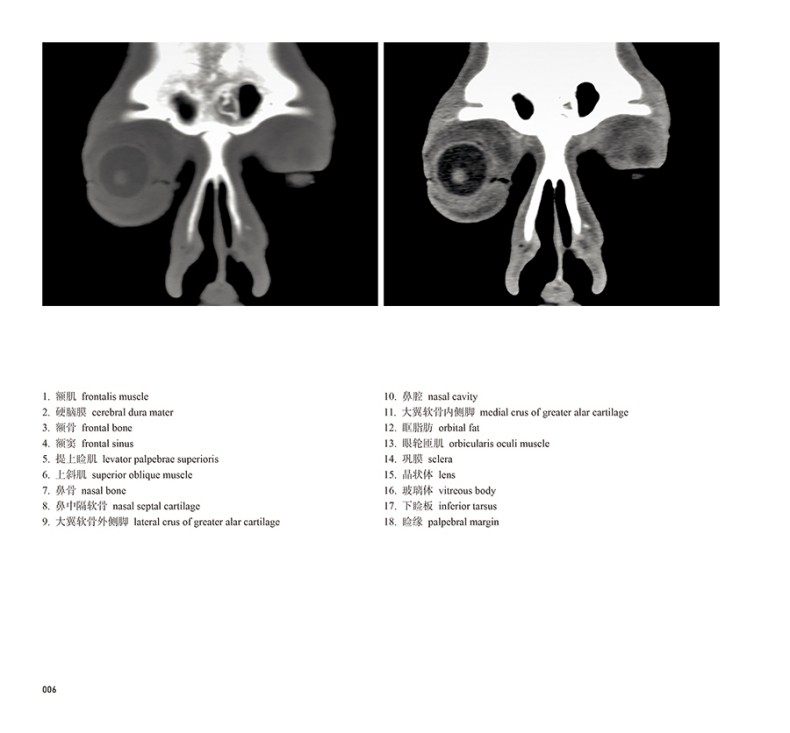

本书从数据集每隔1.2mm选取一幅图像,截取眼、耳、鼻及毗邻颅底的局部区域图像,共112幅图像。同时配以相应部位的CT图像对照。本书特色是断层解剖图利用数字图像处理技术优势,放大并清晰展示眼、耳、鼻及毗邻颅底断面的局部区域结构,组织色泽真实,甚至能够清晰显示肌肉纹理、筋膜纹路等细节结构,图像质量高于美国《人体断层解剖学彩色图谱》(引进版)类似图谱图像质量。对眼科、耳鼻咽喉科医生理解相关解剖结构有较大帮助。